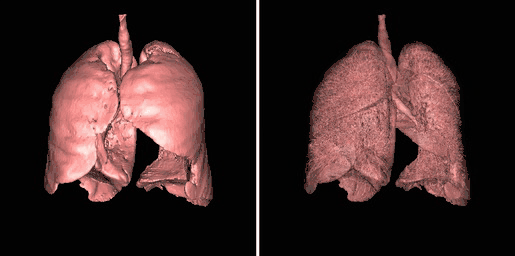

A second example of using an opacity table is shown in the following figure. Here, axial CT data from the patient's airways have been segmented using a region growth technique and the result processed using surface rendering, with full opacity as shown in the left panel and with a reduced opacity (30%) as shown in the right panel:

Notice that internal features of each lung can be discerned when the opacity is reduced. Notice also that continued viewing of this type of transparency display can generate apparent reversal of the image rotation, similar to that noted for the 3D MIPs above. One method of overcoming this type of problem is to segment each lung, for instance. and to blend the results, as illustrated in the following figure: